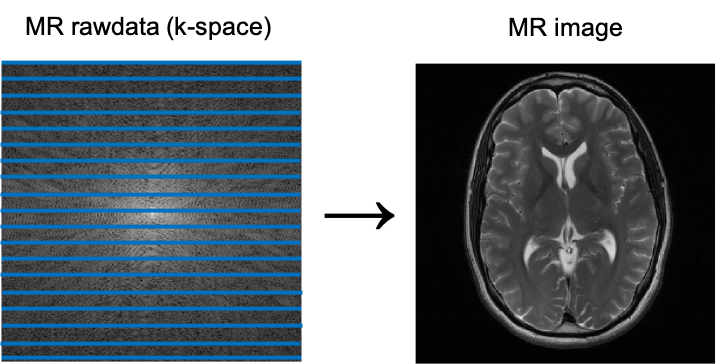

The energy frequencies per location in the imaged plane are transformed into corresponding intensities of gray in the final MRI image, in which high signal intensity is white, intermediate signal intensity is gray, and low signal intensity is black. Once the frequency information in one image plane or slice is gathered, the process starts again for the next slice.

Image 1. K-space and corresponding brain MR Image. Courtesy of Florian Knoll.